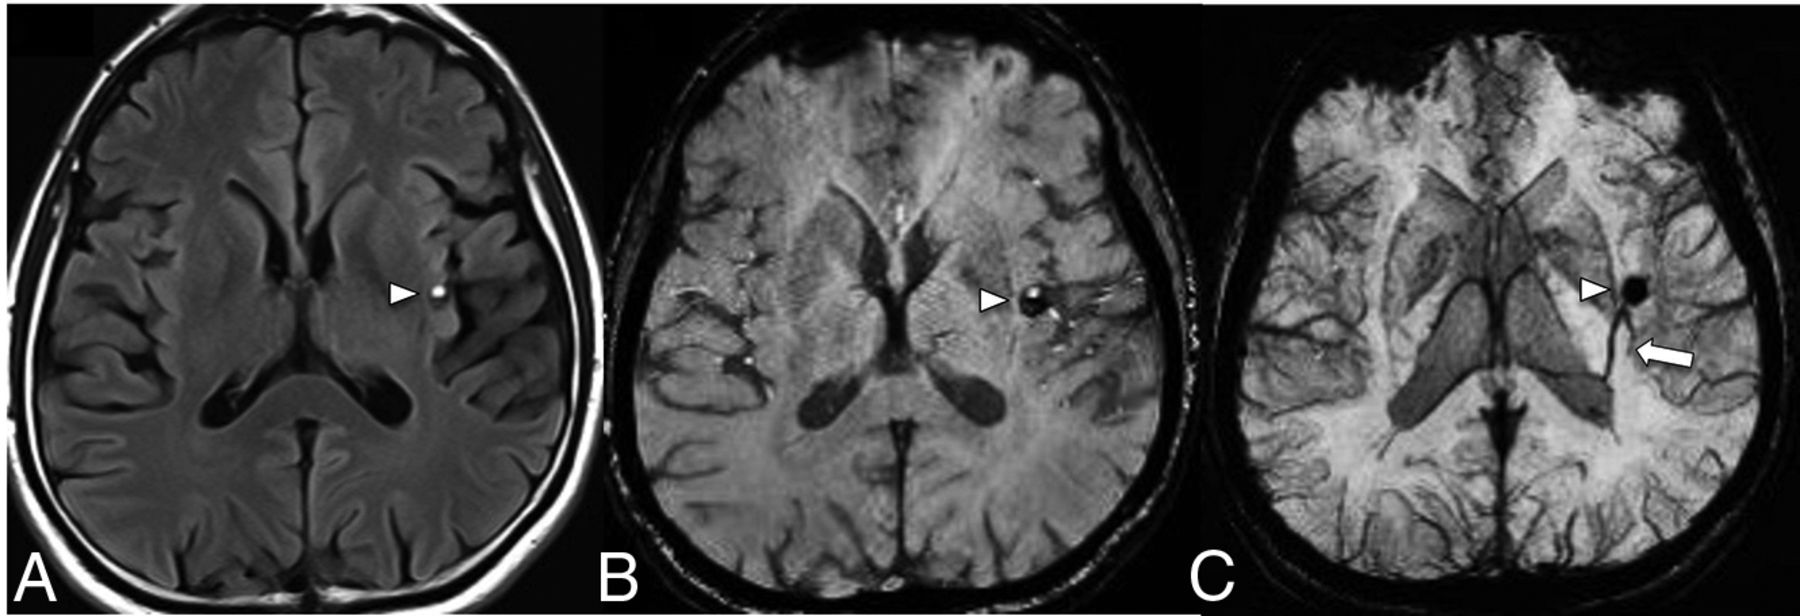

CCMs are vascular sinusoidal lesions lined by a single endothelial layer in a background of a collagenous matrix. CCMs are devoid of arterial or venous communication. They have a strong association with sporadic DVAs, with a frequency of coexistence of between 2% and 33% (Fig 1). The prevalence of CCMs with DVAs also have a positive correlation with increasing age.4 SWI is the ideal sequence to detect DVAs with CCMs due to the increased contrast conspicuity of the deoxyhemoglobin in the venous blood and the presence of blood products in CCMs. The SWI sequence on high-field-strength 7T MR imaging is more sensitive for depicting smaller-sized DVAs associated with sporadic CCMs, which may otherwise not be visible on 3T MR imaging.9

FLAIR (A) shows a mixed-signal-intensity CCM (arrowhead) in the left insular cortex with an internal blood-fluid level and no perilesional edema. A collector vein of a DVA (arrow) is seen from the ventricular ependyma to the CCM, which is barely visible on the SWI (B) and becomes more conspicuous on the susceptibility-weighted MIP image (C).